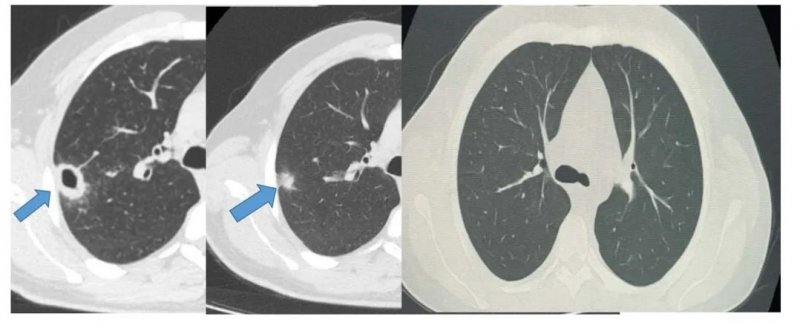

Bayburt Devlet Hastanesi Göğüs Hastalıkları Kliniği’nde, öksürük ve balgam şikayetiyle başvuran 50 yaşındaki hastada kaviter akciğer lezyonu başarıyla tedavi edildi. Malignite ve tüberküloz olasılıkları bronkoskopi ile dışlanarak uygun medikal tedavi başlandı. İki haftalık tedavi sonrası kontrol tomografisinde lezyonda belirgin gerileme gözlendi.

Bayburt Devlet Hastanesi Göğüs Hastalıkları Polikliniği, öksürük ve balgam şikayetiyle başvuran 50 yaşındaki erkek hastada yapılan tetkiklerdeakciğer tomografisinde kaviter (kitlesel) bir lezyon tespit etti.

Hastamız, Göğüs Hastalıkları Uzmanı Uzm. Dr. Hilal Sayma tarafından değerlendirilmiş ve ileri inceleme amacıyla bronkoskopi işlemi uygulanmıştır. Yapılan bronkoskopi sonucunda malignite (kanser) ve tüberküloz olasılıkları dışlanmış, uygun medikal tedavi başlatılmıştır.

İki haftalık tedavi sürecinin ardından yapılan kontrol tomografisinde lezyonda tama yakın gerileme saptanmış, hasta yakın takibe alınmış ve klinik durumu belirgin şekilde düzeltildi.